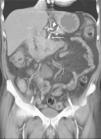

Varias cadenas ganglionares drenan el páncreas. La cabeza de la glándula drena hacia la cadena del surco pancreaticoduodenal y a través de ella, en los grupos ganglionares subpilórico, portal, mesocólico, mesentérico y aortocaval. El cuerpo y cola pancreáticos drenan hacia los grupos ganglionares retroperitoneales, hacia el hilio esplénico, o bien hacia los ganglios de la cadena celíaca, aortocaval, mesocólica o mesentérica. La mayoría de estudios valoran como metastáticas las adenopatías que miden más de 1 cm en su eje corto, no obstante ganglios de tamaño normal pueden contener micrometástasis, mientras que ganglios aumentados de tamaño pueden ser reactivos (fig. 9). Esto supone una importante limitación para la TC que evalúa únicamente en función de parámetros anatómicos. No obstante, como los ganglios regionales a menudo pueden ser resecados en la cirugía no representan una contraindicación quirúrgica formal.

Fig. 9.--Tomografía computarizada en fase pancreatográfica en un paciente con neoplasia de cabeza pancreática que muestra adenopatías de 15 mm de diámetro máximo en región celíaca (puntas de flechas) que resultaron ser reactivas en el estudio anatomopatológico.

Algunos autores han evaluado el rendimiento de la TC en la detección de invasión ganglionar por adenocarcinoma de páncreas14,17,19,32,44, obteniendo valores de precisión diagnóstica de la TC helicoidal bifásica que oscila entre el 58% y el 78,3% para la infiltración tumoral ganglionar. En conclusión, la TC tiene todavía una tendencia hacia la infravaloración de la invasión metastásica ganglionar en parte debida a una alta frecuencia de linfadenopatías reactivas concurrentes. Dado que los ganglios peripancreáticos pueden ser resecados en bloque junto con el tumor primario, la identificación de adenopatías peripancreáticas de tamaño superior a 1 cm en pacientes con tumores por lo demás considerados resecables, no debe contraindicar la cirugía dado el bajo rendimiento de la TC en el diagnóstico de la invasión ganglionar.